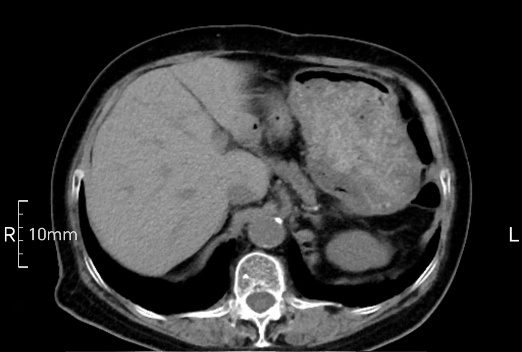

看看下面三幅便知遵醫(yī)囑的重要性。

禁食但檢查前沒(méi)有喝飽,胃未能漲開(kāi),胃壁觀(guān)察效果不佳。